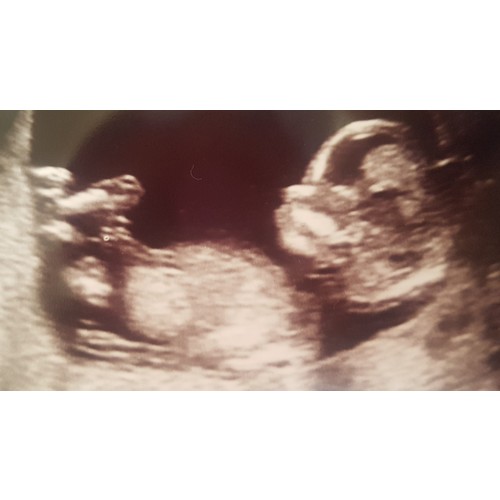

Toen ik precies 15 weken was dacht de gynaecoloog ook een jongen te zien. Ze gaf aan dat het wel vroeg was en dat ze er niet zeker van was. Heb daarom met 17 weken nog een pretecho laten maken en zie de bijgevoegde foto. Kon echt niet missen 😅. Op bijna alle echo's daarna moest die altijd even laten zien dat hij nog steeds een jongen is 🙈.